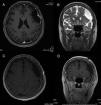

Patients and methodsSix patients with cystic meningiomas were included in the study. All patients underwent a cranial computed tomography scan and magnetic resonance imaging (MRI) evaluation, pre- and postoperatively.

ResultsAll patients presented with long standing headache dating back at least two years. There was no gender predominance in our series. Radiological evaluation revealed two parasagittal and two convexity meningiomas located at the frontal region. Two lesions were located at the tuberculum sellae and the foramen magnum. All of the tumors were totally excised (Simpson Grade I or II). Pathology results included meningothelial meningioma in three patients, angiomatous meningioma in two patients, and metaplastic meningioma in one patient. In two patients, the cystic meningiomas were resected with the use of sodium fluorescein (Na-Fl) under a YELLOW 560nm microscope filter. Na-Fl was found to be very useful in demonstrating the brain–tumor interface, and it was especially effective in resecting the cyst wall of the peritumoural cystic meningiomas. None of the patients had any complications, and no recurrences were noted in any of the patients within the mean follow-up period of 51 months (range: 16–102 months).